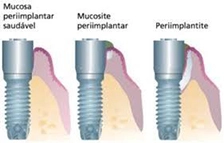

De acordo com o Prof. Dr. Luiz Antônio Pugliesi Alves de Lima, docente da disciplina de Periodontia, FOUSP, a periimplantite é uma doença infecciosa, causada por bactérias da placa bacteriana. Aquela mesmo que temos que remover diariamente, com escova, fio e creme dental, para preservar nossa saúde bucal! Essas bactérias acumuladas sobre os implantes provocam inflamação nos tecidos ao seu redor, levando a destruição do osso ao qual o implante está aderido. Ou seja, prejudicando a osseointegração. É uma doença que se inicia sorrateira e silenciosa, pois não dói, que pode levar a perda do implante! Então, esteja atento e cuide dos seus implantes!

O primeiro estágio desta inflamação é chamado de Mucosite Periimplantar. Neste período, o paciente apresenta apenas uma inflamação na mucosa ao redor dos implantes, que fica mais avermelhada e sangra com facilidade. Ainda não há perda óssea, e o tratamento local realizado por dentista especializado, associado a antissépticos e uma boa escovação e higiene bucal, podem reverter totalmente o problema.

Porém, sem tratamento, a infecção pode evoluir e o paciente pode apresentar mau hálito, inchaço ao redor do implante, pus, sangramento, gengiva avermelhada, bolsas gengivais aprofundadas, e mais importante, perda óssea! Estes últimos sinais podem ser detectados apenas pelo dentista especializado, assim, é fundamental a visita a esse profissional regularmente. Neste ponto, o tratamento local será realizado pelo dentista especializado e poderá incluir: raspagem do implante, associação com antissépticos, uso de antibióticos, e após reavaliação, o paciente poderá ser submetido a um procedimento cirúrgico para a retirada dos tecidos inflamados e recuperação da saúde periimplantar.

Em casos mais graves, a perda óssea ao redor do implante já poderá ter atingido a maior parte do seu tamanho, ou ainda, este poderá apresentar mobilidade. Nesses casos, em que o dente não está mais fixo, é feita a retirada do implante durante a cirurgia. Atualmente, existem alternativas para reabilitar o paciente que tenha adquirido a periimplantite, mesmo que ele perca o implante, uma reconstrução óssea pode ser capaz de repor o osso perdido e possibilitar que o procedimento seja feito novamente.